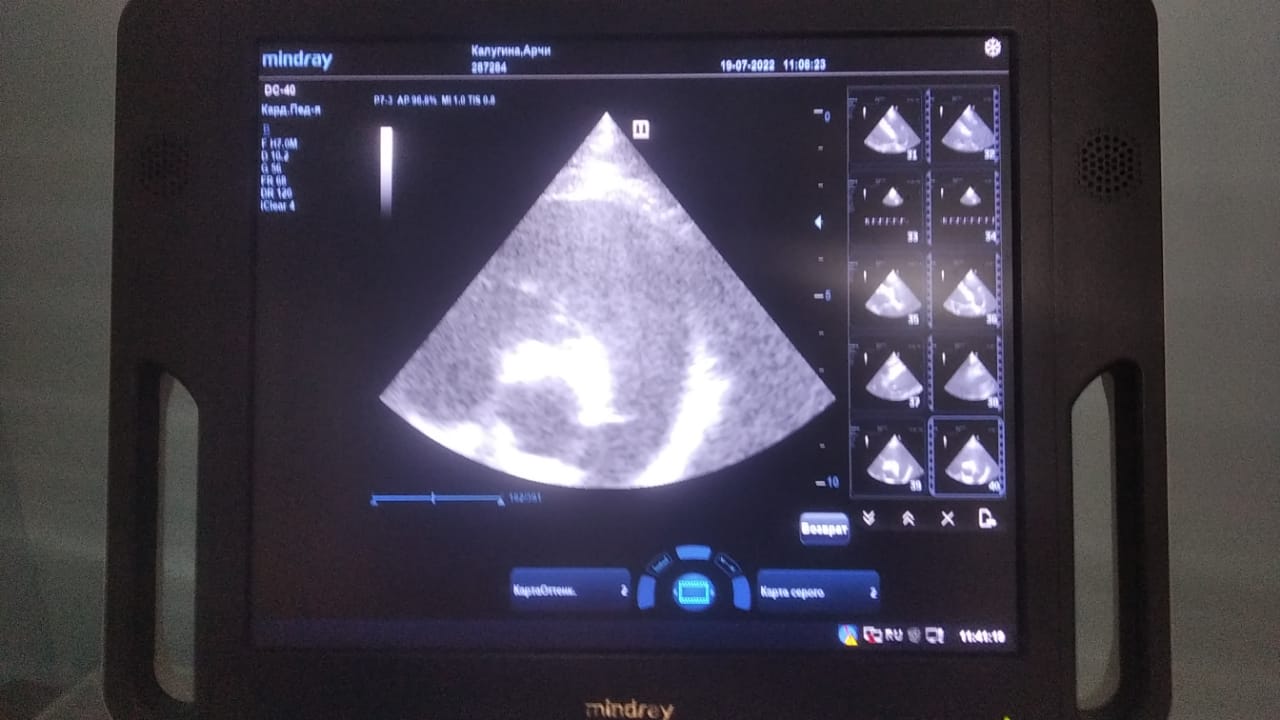

Анализы Арчи. Сердца и легких

Вложения

IMG-20220719-WA0100.jpg

IMG-20220719-WA0102.jpg

IMG-20220719-WA0104.jpg

IMG-20220719-WA0103.jpg

IMG-20220719-WA0105.jpg